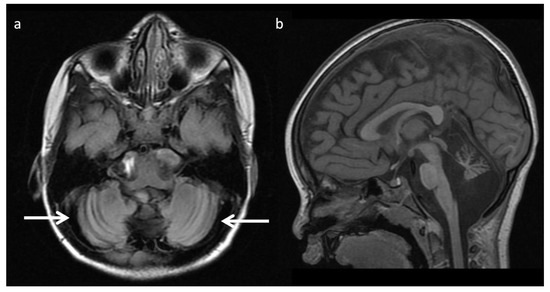

Figure 13.

Zellweger syndrome in a 4-day-old full-term infant with multiple congenital anomalies, hypotonia, and weak/absent reflexes. (a) Axial T2WI shows findings typical of Zellweger syndrome, including bilateral perisylvian polymicrogyria (black arrows), germinolytic cysts (white arrow), and abnormal white matter, which may represent areas of hypomyelination. (b) SV-MRS of the white matter shows elevated Lac (consistent with anaerobic metabolism and indicating active on chronic disease, given MRI appearance), elevated Cho, and depleted NAA and Cr (compatible with neuronal/axonal damage/loss).

Zellweger syndrome (Figure 13): Peroxisomal function is vital to neuronal migration and organization and myelination [9]. PEX gene defects account for most peroxisomal bioassembly disorders, including the milder phenotype, peroxisome biogenesis disorder-1B (PBD1B) comprising neonatal adrenoleukodystrophy and infantile refsum disease. Characteristic MRI findings of Zellweger syndrome include cortical malformations, germinolytic cysts, white matter abnormalities, and reduced gray and white matter volume [3,7,8]. D-bifunctional protein deficiency caused by a disorder of peroxisomal fatty acid beta-oxidation may manifest similar findings. PBD1B also may have overlapping neuroimaging abnormalities, but lacks the systemic findings (e.g., renal cysts, chondrodysplasia punctata) seen in Zellweger syndrome [9]. Dentate hilar/superior cerebellar peduncle involvement progressing to involve the cerebellar white matter more diffusely, the brainstem, thalami, and cerebrum with a posteroanterior gradient typifies the temporal pattern of PBD1B [46]. MRS may show lipid elevation and findings secondary to hepatocellular dysfunction (increased Glu and Gln, decreased mI) [3,8].